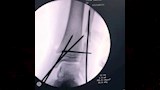

وتضمنت الإصابات كسرًا مضاعفًا في مركز النمو أسفل عظمة القصبة اليسرى، وكسرًا أسفل عظمة الشظية اليسرى، وخلعًا كاملًا في مفصل الكاحل الأيسر، وفقًا لخطورة الإصابات وتأثر مركز النمو، سارع الفريق الطبي إلى اتخاذ قرار بالتدخل العاجل منعًا لتأثير مستقبلي على حركة الطالب أو نمو العظام.

ونجح الفريق في رد الخلع بشكل فوري، أعقبه إجراء عملية تثبيت جراحي للعظام باستخدام أسلاك معدنية، وسط متابعة دقيقة لضمان إعادة العظام إلى موضعها الطبيعي وتفادي أي مضاعفات محتملة، إذ أسهمت سرعة التدخل ودقته في استقرار حالة الطالب سريعًا، قبل أن يغادر المستشفى في حالة جيدة بعد تلقيه الرعاية الطبية الكاملة.